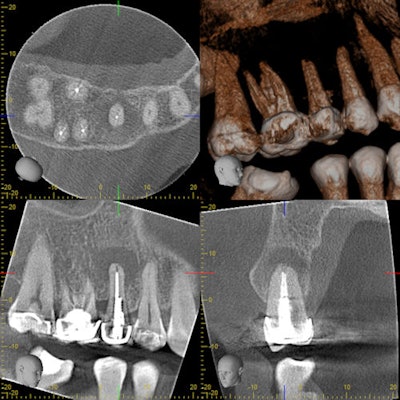

The CBCT indicates an acute apical abscess on a prior endodontically treated tooth.Dr. Deepika Ganne.